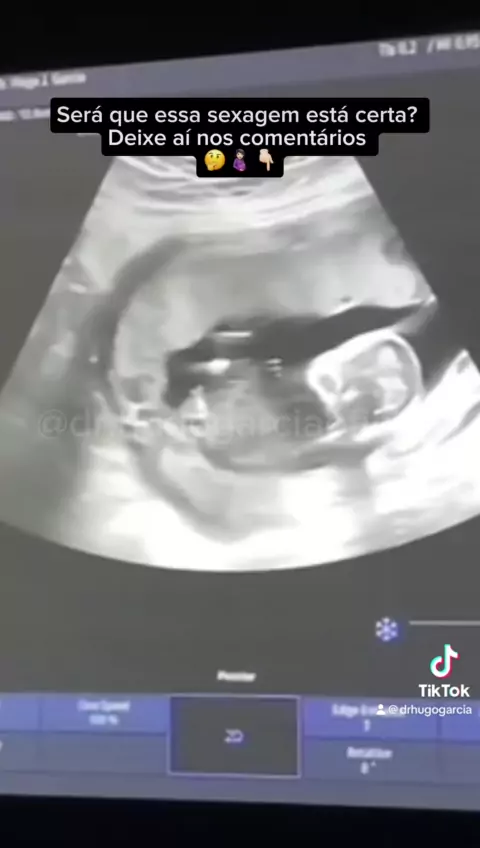

E aí!! A sexagem ta certa????